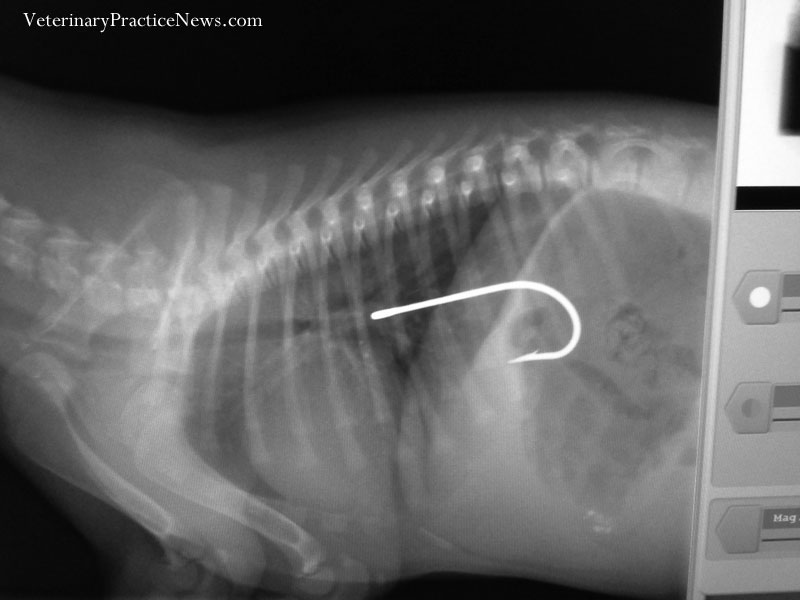

From www.veterinarypracticenews.com

2014 XRay Contest Winners Veterinary Practice News Will A Fish Hook Dissolve In A Dog S Stomach Or she investigates a colorful fly or. If the fishhook is in the esophagus or stomach, a dog may gag, retch, vomit, stop eating, drool, have difficulty swallowing, or experience weight loss or dehydration. A hook will rust away in a fish, but it may take a while, especially if the hook is plated or made of thick metal. One. Will A Fish Hook Dissolve In A Dog S Stomach.